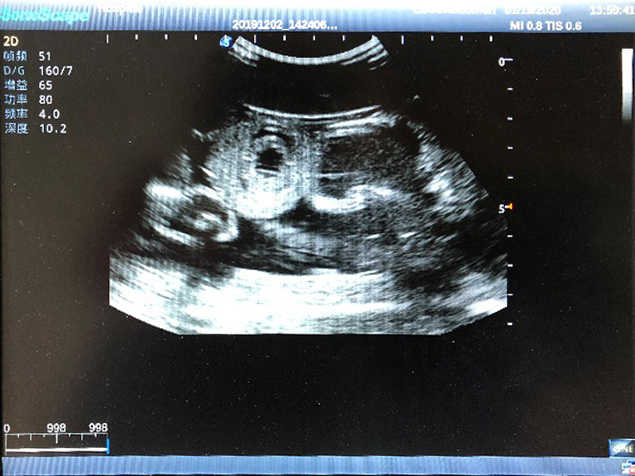

1)  Ideal for trainings like ultrasound-guided abdominocentesis with visible ascites flowing out, ultrasound-guided femoral artery & venous puncture

2)  High quality ultrasound image with clear structures like gallbladder, liver, intestines, arteries and veins etc.